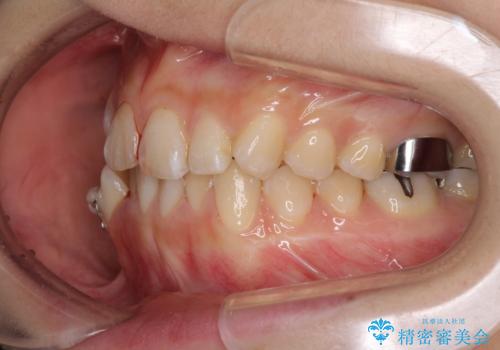

- 上下の八重歯を気にして来院された患者様です。

上下ともに八重歯の後ろの歯を1歯ずつ抜歯し、補助装置(リンガルアーチ)を用いて八重歯の位置を改善し、その後インビザラインにより矯正治療を行うこととしました。

途中海外留学をされたため、治療期間は長くなりましたが、事前に補助装置やワイヤー装置を併用したことで、きれいな歯列に仕上げることができました。